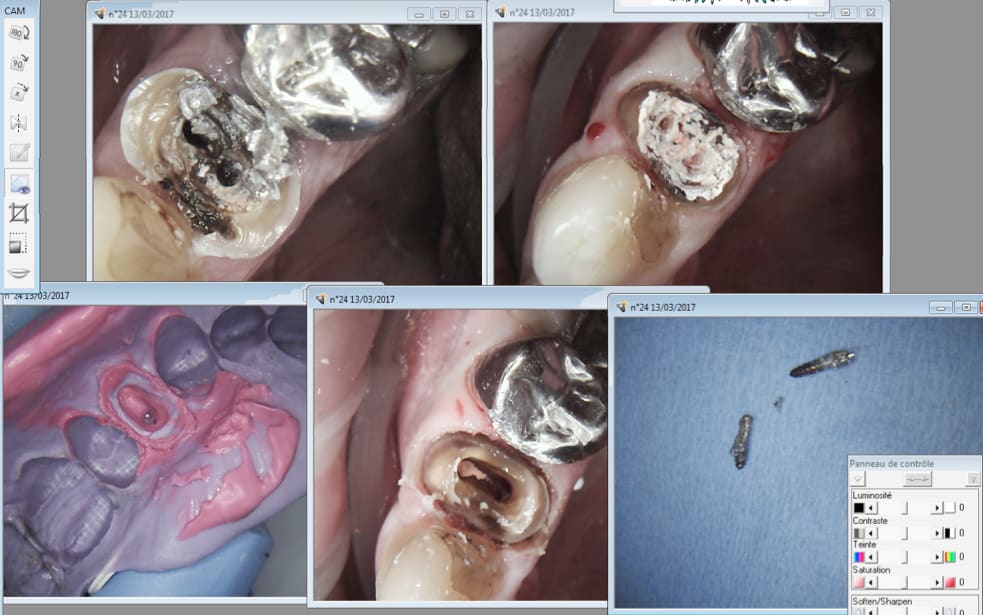

chicot29

Casa je viens encore de reprendre un de tes traitements. Appliques toi merde ! -)))

13/03/2017 à 12h20

Ici les 2 vont avoir droit à leur ic coiffe ( CMU) et pourtant un ic tarif CMU ca ne rapporte pas bésef.